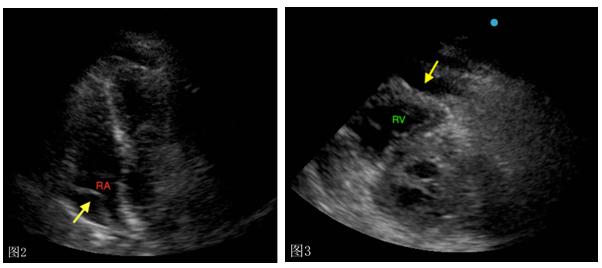

床旁即时超声(POCUS)检查显示中度心包积液以及右心房(图2)和右心室(图3)舒张期塌陷,下腔静脉(IVC)直径增加不随呼吸期变化(图4)。

(图2、图3 POCUS检查)